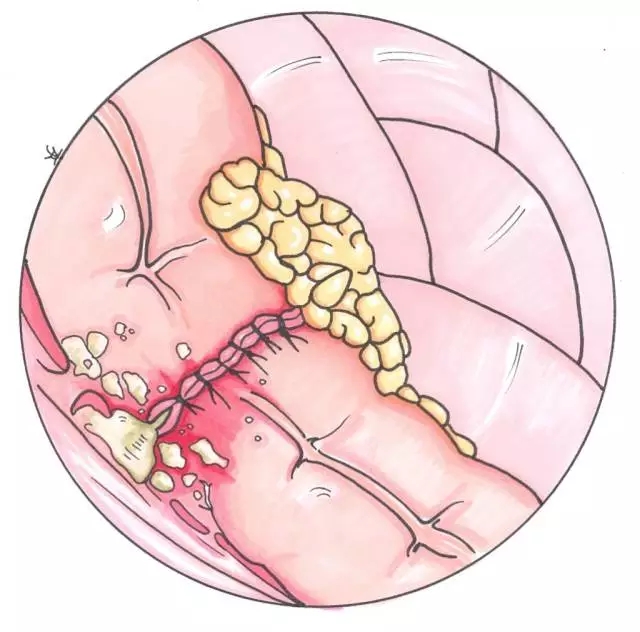

多中心,前瞻性研究395例0/I期直肠癌病人,在接受腹腔镜低位前切除加双吻合器技术术后,吻合口瘘的发病因子。采集的变量数据包括病人的背景情况、肿瘤和手术因子,记录病人发生吻合口瘘的各种情况,对临床研究数据进行单因素和多因素分析,来确定吻合口瘘的相关风险因子。

总体吻合口瘘的发生率为8.4%,单因素分析显示男性(P=0.006)和围手术期血糖水平(P=0.0034)显著地与吻合口瘘相关。根据P值小于0.2的因子,采用多因子分析,包括性别,围手术期血糖水平,美国麻醉医师协会(ASA)分类(P=0.15),经肛门放置减压肛管(P=0.06),以及横断直肠使用的切割吻合器的钉仓数(P=0.18)。多因素分析确定男性(让步比4.12, P=0.006)和术后不放肛管(让步比3.11,P=0.048),是预示吻合口瘘的独立风险因子。

男性和术后不放肛管显然是造成吻合口瘘的独立风险因子。放置肛管或许能帮助预防腹腔镜低位前切除术后吻合口瘘,特别是男性病人。